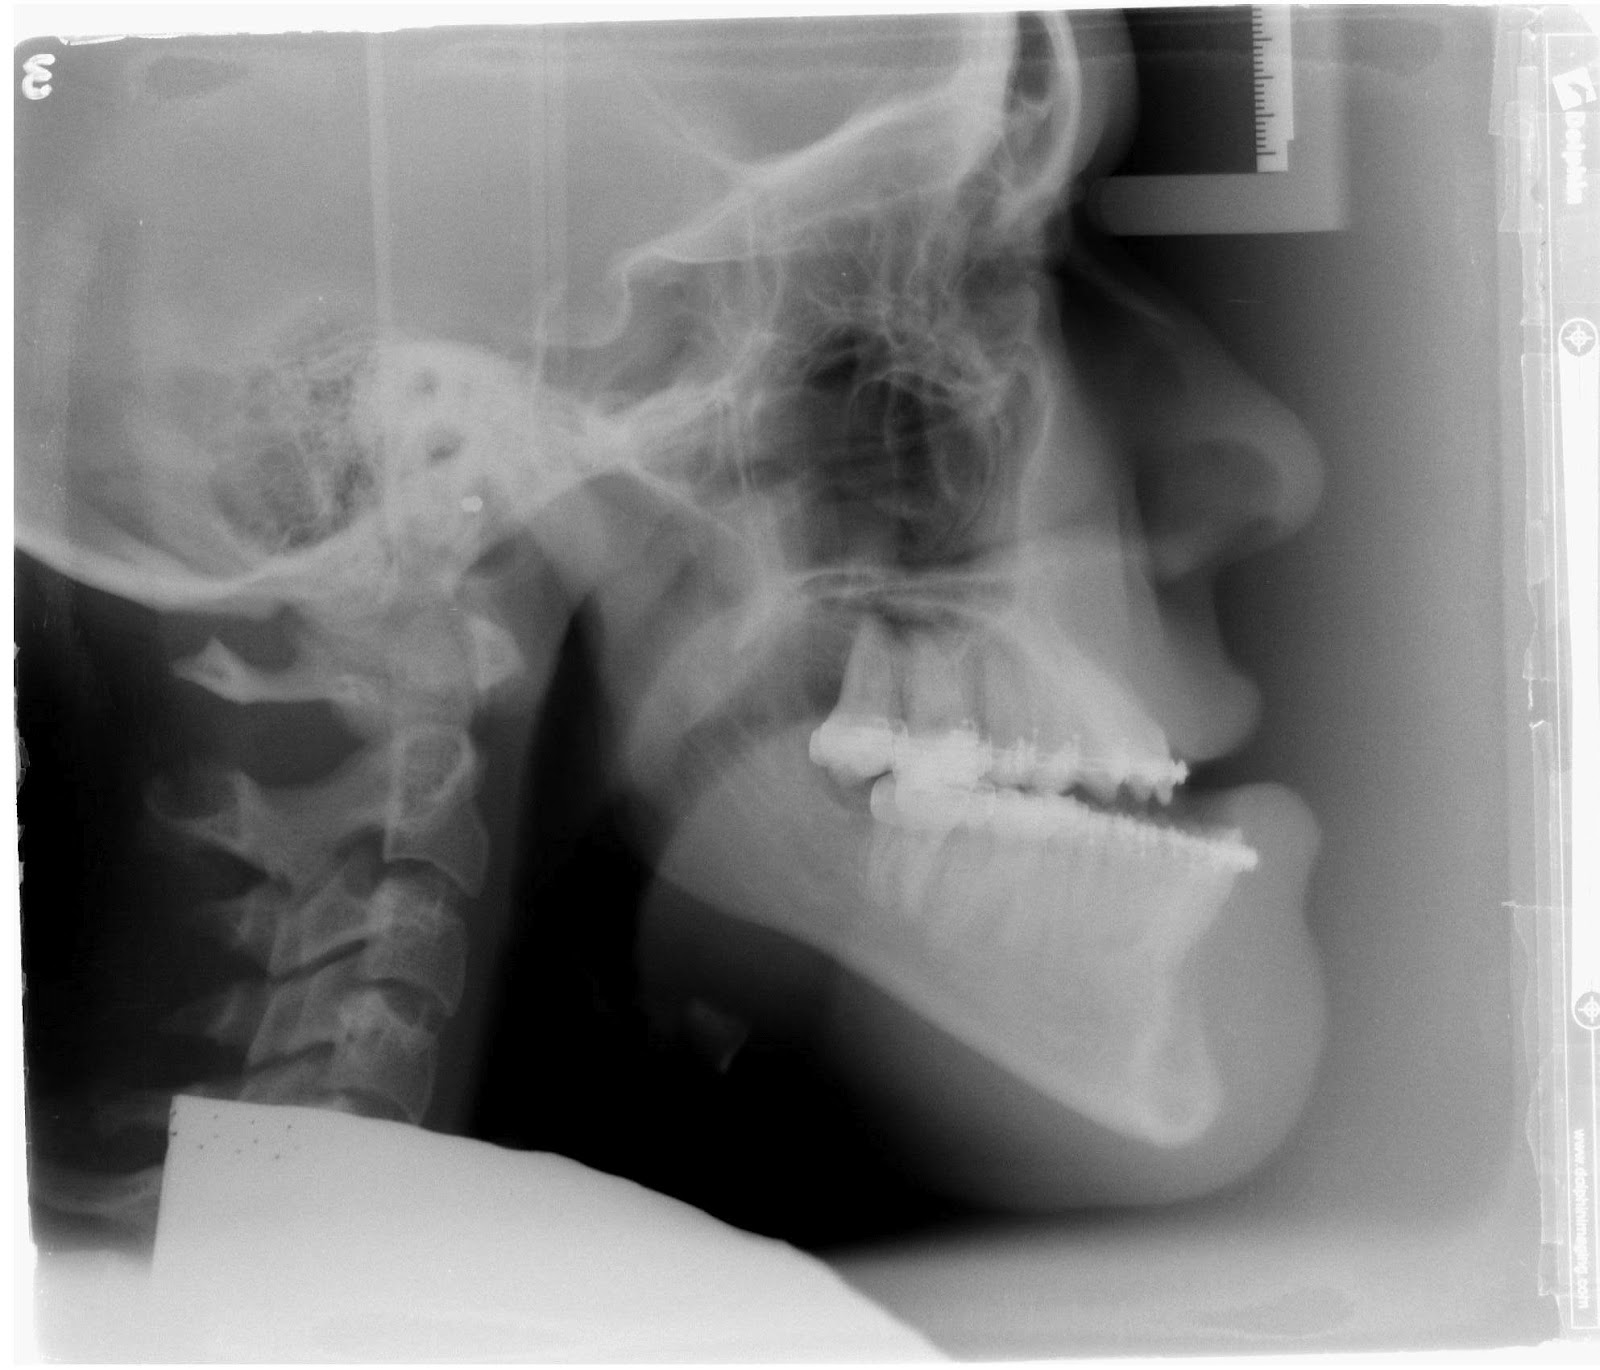

Underbite X Ray . Here, we’ll talk you through everything that you need to know about this type of dental malocclusion and how it may affect you or your child. these diagnostic tools offer a complete view of the jawbone, tooth roots, and surrounding structures. an underbite is a general term used to describe the state of the lower teeth protruding over the top teeth. In dentistry, an underbite is considered a class iii malocclusion. learn about the causes of an underbite, as well as its impact on quality of life, and how an underbite is commonly treated by doctors, including details about common surgical approaches. an underbite is when the bottom teeth extend forward, giving the appearance that the jaw is pushing outward from the mouth. let's delve into the world of underbites, understanding its causes, recognizing its symptoms, and comprehending the diagnostic procedures. An underbite can be mild or severe and will require dental treatment to fix, as they rarely fix themselves naturally. an underbite is when the lower part of your jaw juts out farther than the upper part. it is possible to fix an underbite in adults and children; A malocclusion categorizes a variety of different teeth misalignments and malformations. Surgery and dental braces are common treatment options, along with some others.

Underbite Surgery Xray Underbite X Ray these diagnostic tools offer a complete view of the jawbone, tooth roots, and surrounding structures. an underbite is when the bottom teeth extend forward, giving the appearance that the jaw is pushing outward from the mouth. Surgery and dental braces are common treatment options, along with some others. An underbite can be mild or severe and will require. Underbite X Ray.